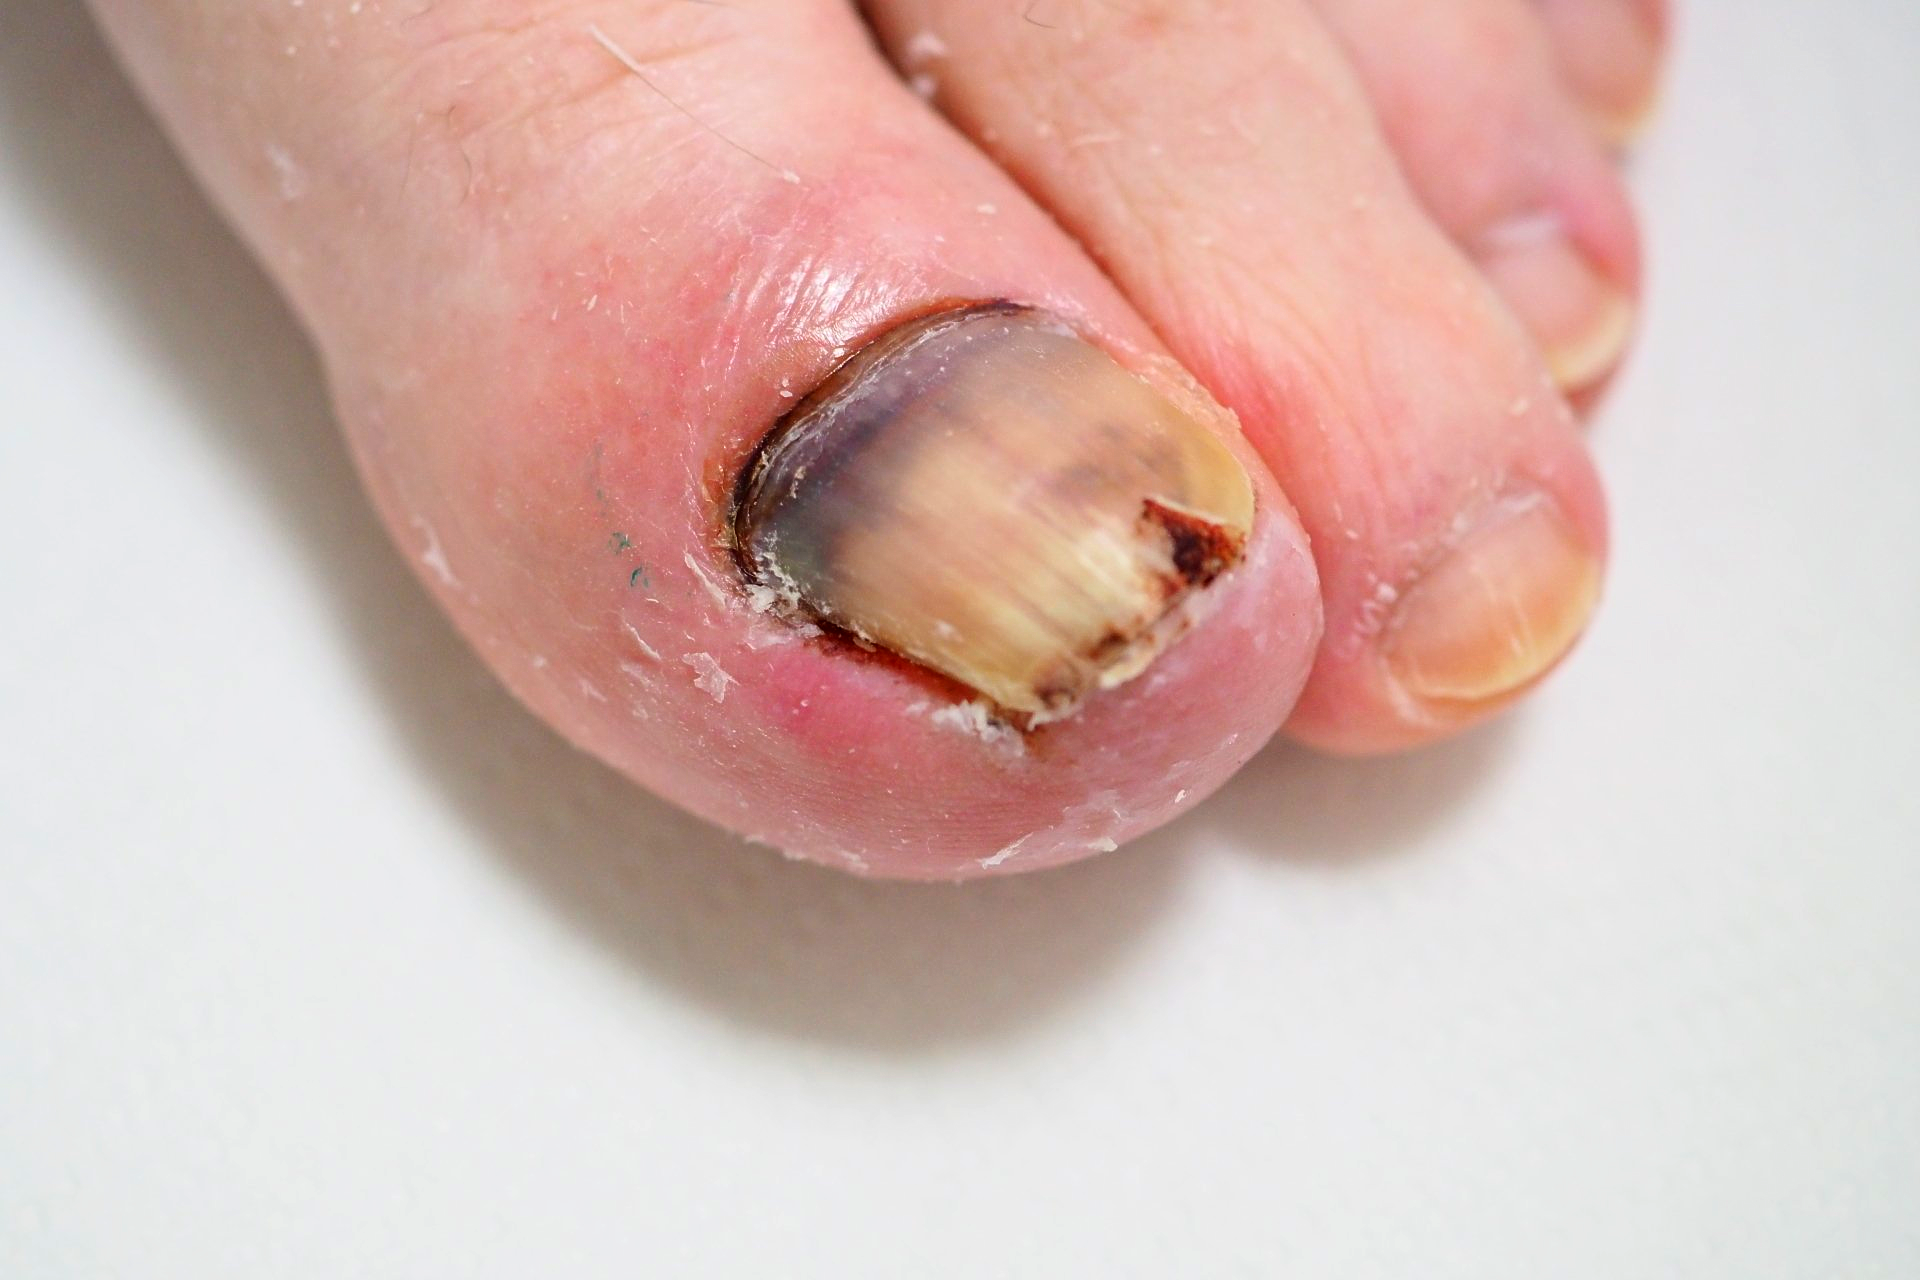

1.) Akutfall am Nagel

👉 Im Folgenden ein Akutfall der besonderen Art:

Kommt nicht sehr oft aber doch immer wieder einmal vor.

🔴 Der Nagelspan kommt bereits DURCH das Weichgewebe.

In Vergrößerung am Monitor auf Bild 2